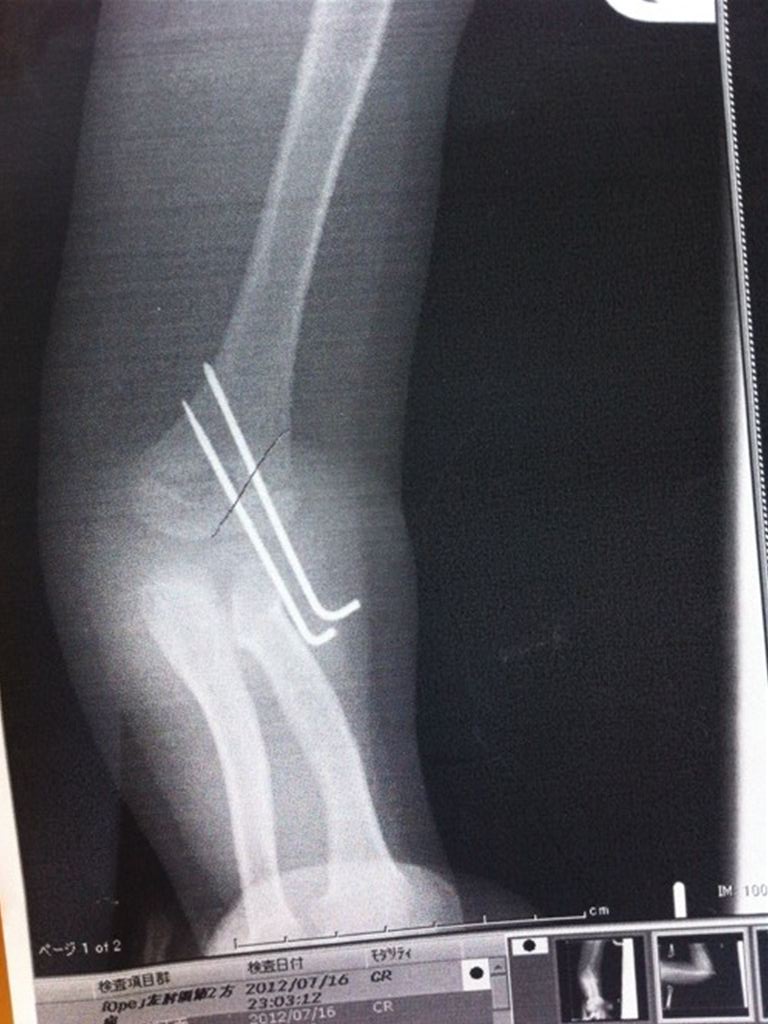

術後のレントゲン。

黒いボールペンの線が折れた箇所。

針金で固定されております。。。

痛々しいですね・・・。